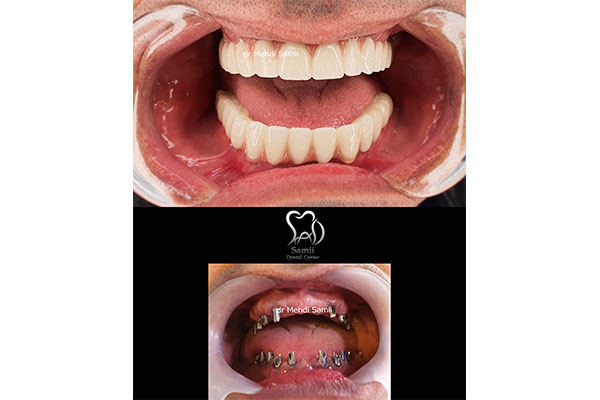

ایمپلنت دیجیتال روشی بسیاری جدی و نوین برای جایگزینی دندان و کاشت ایمپلنت است و مزیت های بسیاری نسبت به کاشت ایمپلنت معمولی دندان دارد. در این روش دندانپزشک به صورت کامل در کوتاه ترین زمان ممکن ایمپلنت دیجیتالی و پروتز دندان را با بالاترین کیفیت توسط داده های کامپیوتری که از اسکن دهان و فک شما گرفته می شود طراحی میکند و این طراحی باعث می شود تا محل دقیق کاشت دندان شما مشخص شود.

ایمپلنت دیجیتال دقت بسیار بالایی دارد و برای افرادی که تعداد ایمپلنت دندان بالایی دارند، به صورت بسیار آسان و دقیق عمل میکند و نتیجه ای فوق العاده طبیعی و شبیه به دندان های اصلی می دهد. این روش دارای ظرافت و زیبایی بوده و کمترین میزان درد را در میان سایر کاشت های ایمپلنت دیجیتال دارد. اگر شما نیز ساکن تهران هستید و به دنبال مرکز ایمپلنت دیجیتال در تهران هستید ادامه این مطلب را از دست ندهید.

همانطور که اشاره کردیم، معمولا برای پر کردن ناحیه بی دندانی یا جایگزین کردن دندان از دست رفته، به جز پروتزهای متحرک یا به وسیله بریج (روکش های متصل به هم) استفاده می شود و یا از کاشت دندان یا ایمپلنت استفاده می گردد. ایمپلنت به روش پانچ نوعی جراحی ساده کاشت دندان میباشد با کمترین درد و خونریزی انجام می شود.این روش برای افرادی کاربردی است که دارای بافت نرم در لثه و بافت محکم در استخوان داشته باشند. ایمپلنت دیجیتال دارای ظرافت و درصد خطایی پایین تری است و رضایت بیماران بیشتری دارد. در معرفی مراکز ایمپلنت دیجیتال در تهران، لیست کامل را برای شما قرار خواهیم داد. هم چنین برای مشاهده بهترین پزشکان برای ایمپلنت در شمال تهران می تواند به صفحه مربوطه مراجعه نمایید.

ایمپلنت یک روزهیک روش کاشت ایمپلنت است که به منظور جایگزین دندان های از دست رفته و شکسته مورد استفاده قرار میگیرد پایه های ایمپلنت شبیه ریشه دندان های طبیعی در استخوان فک عمل کرده و پایه بسیار مستحکمس برای سوار کردن تاج های دندانی که ظاهر شبیه دندان های طبیعی دارند بوجود می آورد.در روش های کاشت ایمپلنت سنتی دوره بهبود پس از کاشت پایه و پیش از نصب تاج دندان بسیار طولانی است در صورتی که فرایند ایمپلنت یک روزه روشی کاملا خاص و کاربردی است .

که با اسفاده از ان جای خالی دندان در یک روز توسط پایه ایمپلنت و تا دندانی پر می شود. البته در روش کاشت ایمپلنت فوری تاج دندان موقتی تا زمانی که تاج دندان اصلی برای نصب اماده شود روی پایه سوار میشود و زیبایی دندان های شمارا تکمیل می کند.